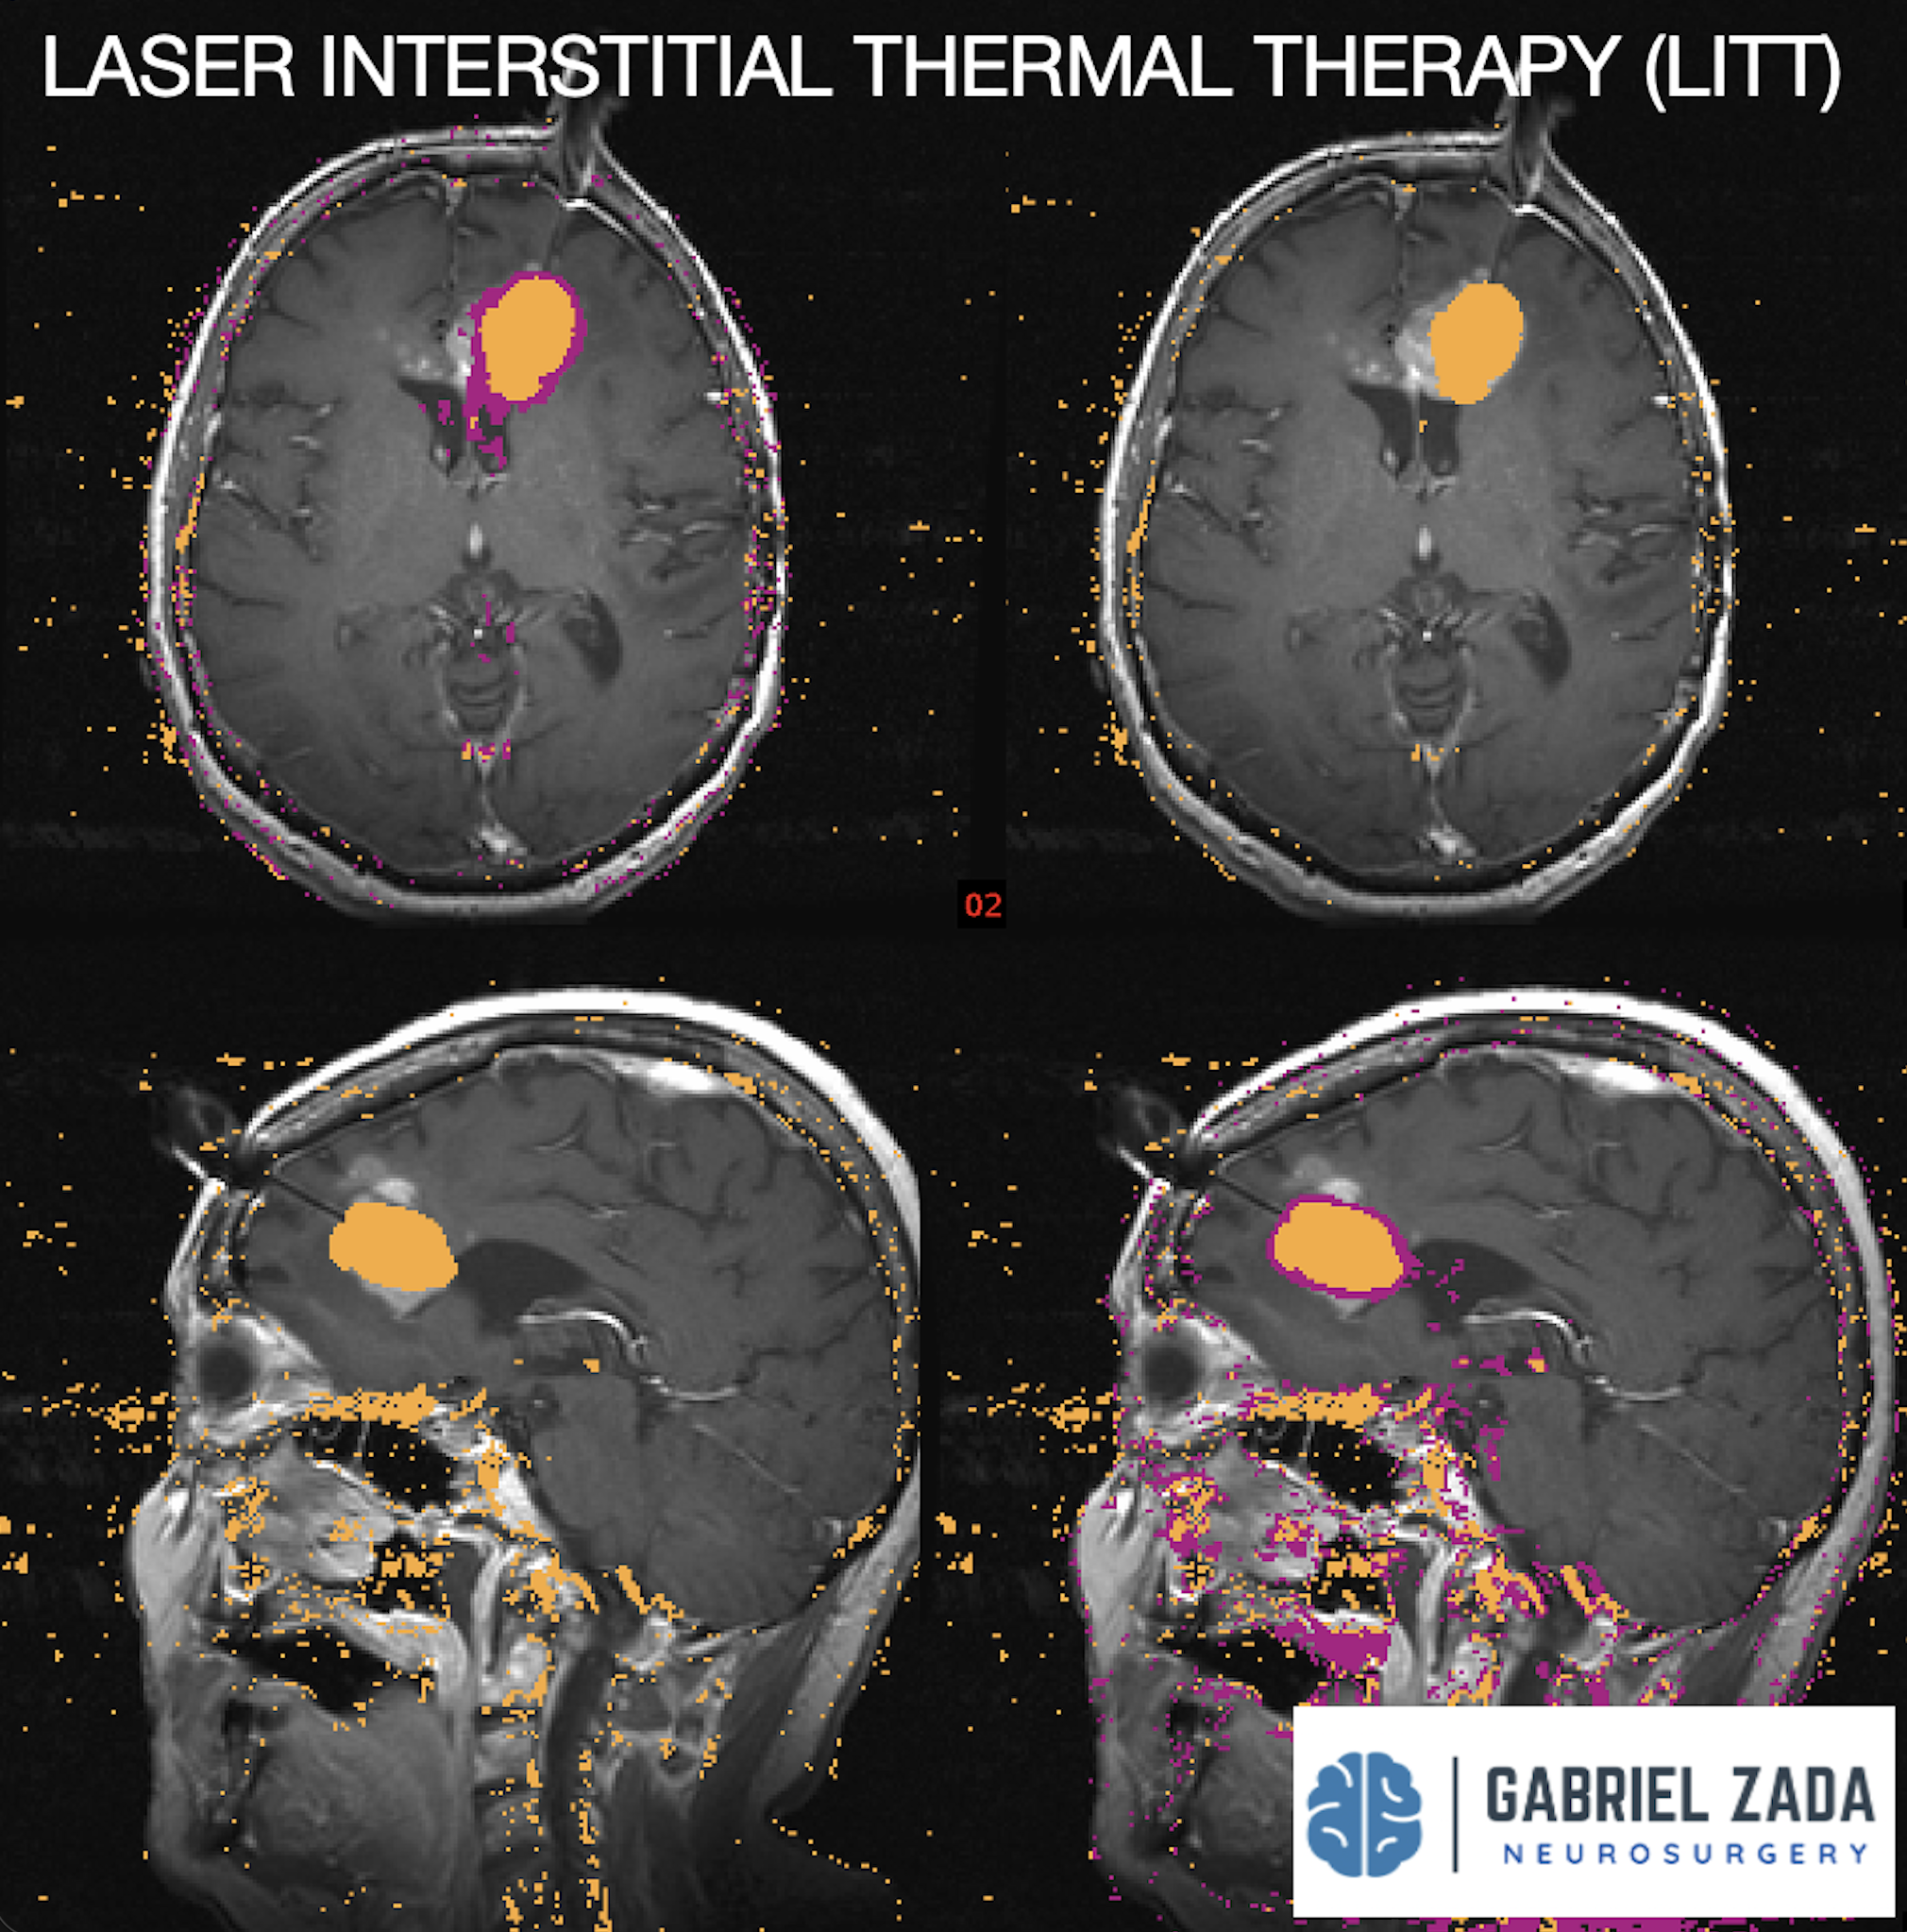

Explore this comprehensive gallery featuring pre‑ and post‑operative imaging of patients with skull‑base tumors treated by Gabriel Zada, MD, MS, FAANS, FACS. These cases highlight Dr. Zada’s expertise in advanced neurosurgical techniques and outcomes.

*Representative cases shown for educational purposes. All images de-identified. Individual results vary.